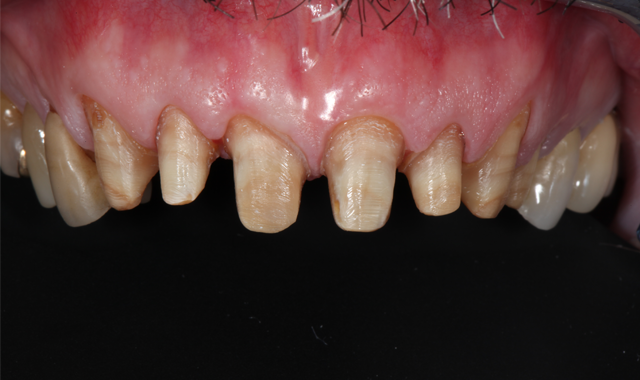

Fig. 8

Fig. 9

During the second appointment, the teeth were prepared (Figs. 8 and 9) and digital scans taken (Figs. 10 and 11). The milled provisionals were relined, cemented and customized, enabling the patient to “test-drive” the proposed treatment and share his desired alterations prior to fabricating the permanent restorations. The patient completed a one-week trial period and, upon returning, requested modifications to the maxillary provisionals, which were made.